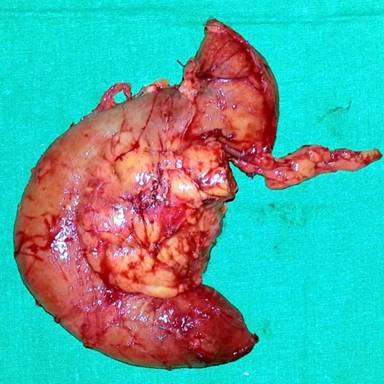

A previously well 24-year-old male presented with a one month history of rapidly progressive obstructive jaundice associated with abdominal pain suggestive of a biliary colic. He was otherwise well except for anorexia of the same duration. His past medical and family history were unremarkable except for receiving treatment for meningitis two years back. General examination revealed he was deeply icteric, but free of supraclavicular lymphadenopathy and features of chronic liver disease. Abdominal examination showed tender hepatomegaly with a palpable gallbladder but no free fluid. His liver functions were deranged with significantly elevated serum bilirubin and alkaline phosphatase levels. Trans-abdominal ultrasonography showed a suspicious pancreatic head mass, a dilated common bile duct (1.8 cm) and a distended gallbladder with no calculi. Contrast-enhanced CT (CECT) of the abdomen revealed a pancreatic head mass encircling the main pancreatic duct and CBD opening. Tumor also extending into the duodenal wall through muscularis propria without evidence of superior mesenteric or portal vessel involvement nor distal metastases. The pancreatic duct showed significant dilatation but there was no intraductal parenchymal calcification (Figures 1 and 2). These findings were corroborated by upper gastrointestinal endosonography. Pre-operative ERCP and stenting was done for nutritional optimization prior to surgery. Based on a preoperative diagnosis of an ampullary malignant stricture a standard pancreaticoduodenectomy (Whipple’s procedure) was performed. During surgery, the entire pancreas was found to exhibit a hard texture but there was no evidence of peritoneal or liver metastases. Postoperative recovery was uneventful except for a minor (ISGPF – grade A) pancreatic fistula which resolved with conservative management. The resected specimen (Figure 3) showed an irregular, solid, whitish mass measuring 4.4x3.0x3.0 cm. Histology demonstrated a lesion composed of nests of small round cells with scanty cytoplasm surrounded by prominent desmoplastic stroma, compatible with a poorly differentiated DSRCT of the pancreatic head (Figure 4). The resection margin was positive and there was perineural and vascular invasion. The tumor cells were negative for synaptophysin and chromogranin but positive for desmin and cytokeratin (Figure 5). Peripancreatic lymph nodes were positive for the tumor deposits. He received adjuvant combination chemotherapy that included vincristine, cyclophosphamide, doxorubicin, ifosfamide and etoposide. Clinical assessment and CECT done six months after surgery showed him to be well with no evidence of disease progression.

Figure 3. Resected surgical specimen with the tumour. |